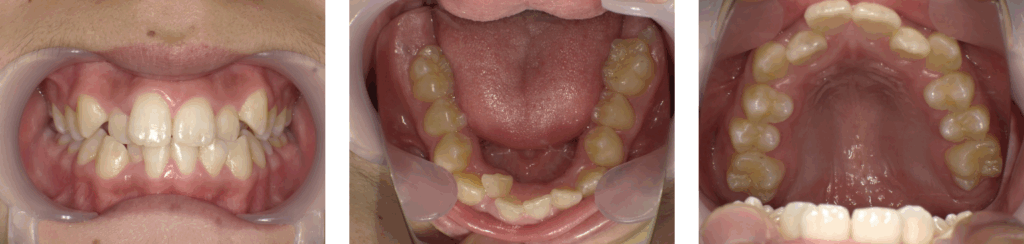

症例2:急速拡大装置のみ使用した症例

| 年齢 | 11歳 |

| 性別 | 男子 |

| 治療の理由(主訴) | ガタガタの見た目を治したい。 目立つのでワイヤー装置は付けたくない。 |

| 治療方法 | 顎顔面矯正 |

| 治療期間 | 1年4か月 |

| 費用 | 44万円 |

治療前